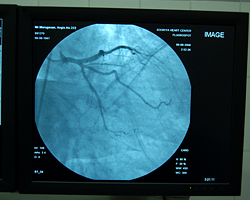

Cardiac Cath Lab

The Cardiology lab department is equipped with Siemens machine with the facilities for angioplasty both coronary and pherepheral, permanent pacemaker implantation and ICD implantation, which is operated by qualified professionals intensively focused on their own sphere of service.

Cardiac Cath Lab Inauguration Pictures